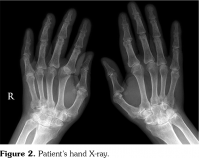

A 45-year-old male patient with RA was referred for newly onset skin rashes on his arms and legs after starting the treatment with tofacitinib (Figure 1). He was taking methotrexate 5 mg/weekly, folic acid 5 mg/weekly and tofacitinib 5 mg twice a day for RA. Disease had started nine years ago, first with pain and swallowing on his ankle. Within one year, arthritis developed on wrist, metacarpophalangeal (MCP) and proximal interphalangeal (PIP) joints, with no involvement in distal interphalangeal (DIP) joints. The patient had no inflammatory back pain symptoms. Psoriasis was not present in his or his family’s medical history. Laboratory tests were negative for antinuclear antibody, extractable nuclear antigen profile, anti-cyclic citrullinated peptide, rheumatoid factor and human leukocyte antigen B27. Erythrocyte sedimentation rate was 26 mm/hour and C-reactive protein was 12.6 mg/L (0-5 mg/L). There were bilateral ulnar styloid erosions, carpal erosions and osteopenia on his hand X-ray; marginal erosions on fifth MCP, second MCP, third PIP joint, subluxation on second MCP joint on right hand; joint erosion and subluxation of first MCP, erosion and joint space narrowing of second PIP joint on left hand (Figure 2). DIP joints were normal on both hands except two osteophytes. On his pelvis anteroposterior X-ray, sacroiliac joint spaces were normal (Figure 3). Patient’s type of joint involvement and radiological findings were consistent with RA but not psoriatic arthritis. In this course, he had used methotrexate, sulfasalazine, leflunomide, hydroxychloroquine and glucocorticoids at different times. Because of the ineffectiveness of the conventional synthetic disease-modifying anti-rheumatic drugs, etanercept was started. Then, etanercept induced skin rashes with unknown characteristics and was stopped subsequently. After improving of the skin rashes, rituximab was started but discontinued due to the ineffectiveness. Tofacitinib was started when his disease activity was high (disease activity score-28 [DAS28] >5.1). Skin rashes appeared on the third month of the tofacitinib therapy while disease activity was low (DAS28=2.8). We consulted the dermatology. Dermatological examination revealed multiple, clearly demarcated, silvery, squamous and erythematous papules and plaques on the arms, legs, and ankles. Skin biopsy was performed. Epidermal parakeratosis, hyperkeratosis, focal hypogranulosis, and acanthosis with elongation of the rete ridges were observed in the skin biopsy. He was diagnosed with psoriasis. We decided that tofacitinib induced psoriasiform lesions, so tofacitinib was discontinued and leflunomide was started. After two months, lesions were improved. A written informed consent was obtained from the patient.